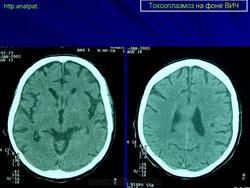

Токсоплазмоз у ВИЧ - инфицированных

Церебральный токсоплазмоз

Токсоплазмоз

Neurotoxoplasmosis

Дифференциальная диагностика изображения